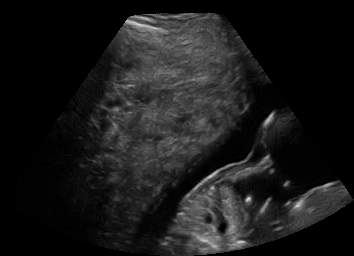

Real in-vivo images. 22 ultrasound sequences were collected using a GE Voluson E8 machine during standard fetal screening exams of 8 patients. Each sequence is several seconds long. We extracted all 4427 frames and resize them to , see Fig. 2 for some examples. The resulting image set was randomly split into training-validation-test sets by a 80-10-10% ratio.